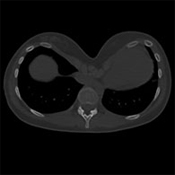

Cálculo del índice de Haller de un Pectus

El índice de Haller se estableció en 1987 para evaluar la importancia de un Pectus a partir de un cálculo realizado en una imagen digital. Se calcula a partir de un corte de escáner en el punto más profundo de la depresión: es la relación entre el ancho y la profundidad máxima.

Permite medir la profundidad del Pectus Excavatum con mayor precisión, particularmente en mujeres donde la deformación es difícil de evaluar debido al volumen mamario. Cuanto más alto es el índice de Haller, más profundo es el Pectus Excavatum

Es práctico y sigue siendo utilizado, pero proporciona una idea imperfecta de la importancia de la depresión y no predice ningún posible y raro impacto funcional del pectus.